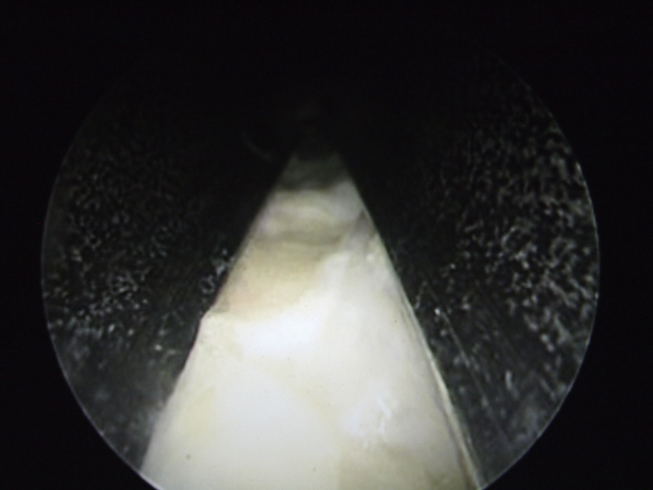

Fig. 4.

The intermetatarsal nerve was seen by rotating the slotted cannula and scope, facing 6 o'clock in the plantar position.